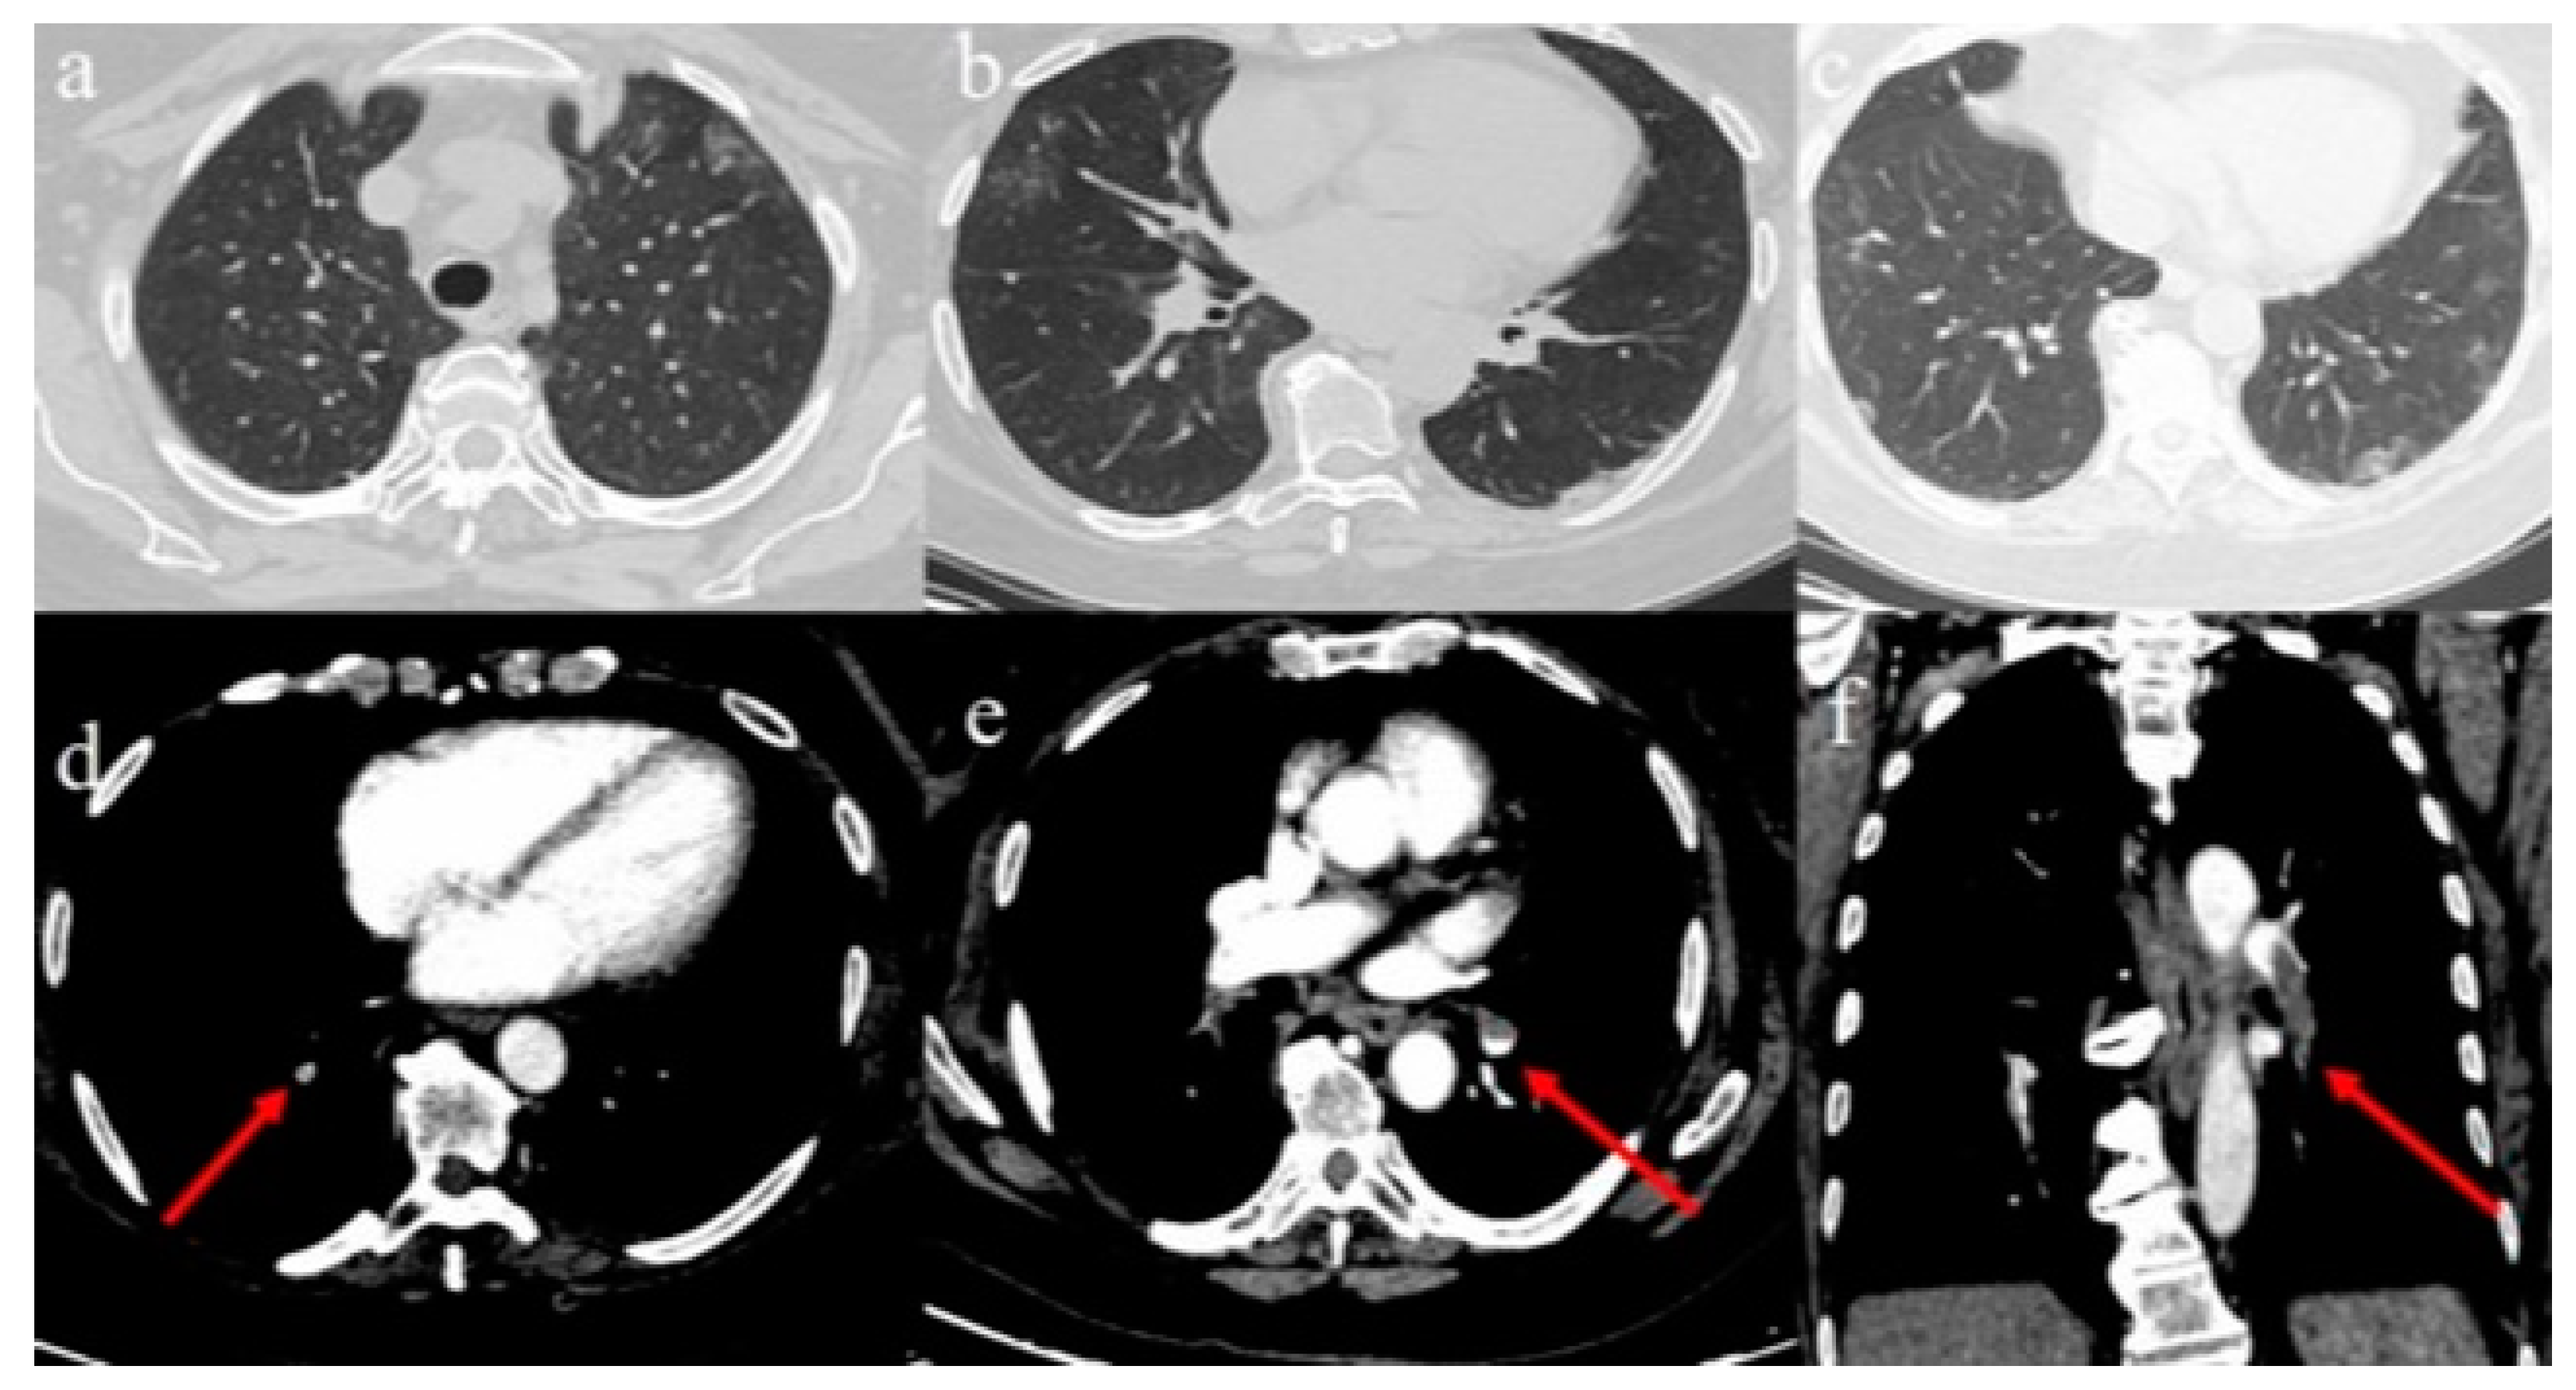

2.1. Case 1

2.2. Case 2